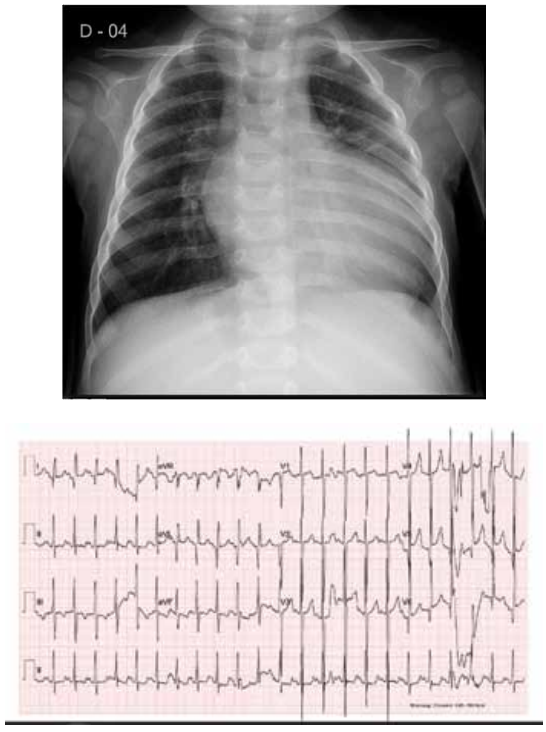

Com base na radiografia de tórax e no eletrocardiograma de um lactente de 9 meses, apresentados a seguir, qual é a malformação cardiovascular mais provável?

(Arquivo pessoal; imagem usada com autorização)

Origem anômala de artéria coronária esquerda da artéria pulmonar.

Valva aórtica bicúspide com estenose.

Atresia da valva pulmonar com septo interventricular íntegro.

Tetralogia de Fallot.

Estenose congênita da valva mitral.